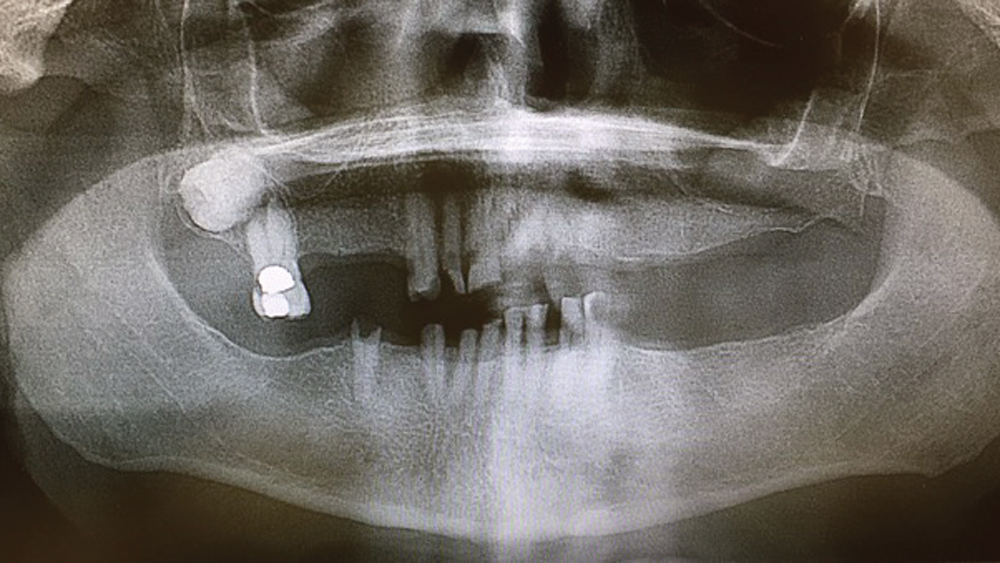

To establish the foundation needed for a screw-retained restoration and avoid fracturing the facial plate, clinicians must position the immediately placed implant against the lingual or palatal wall of the extraction socket. This is one of the reasons I designed the Hahn™ Tapered Implant (Glidewell Direct; Irvine, Calif.) with deep, sharp threads, which enable precise directional control during insertion and prevent the implant from “walking” toward the facial plate as it is threaded into place. This thread design also leads to high primary stability in all bone types, which is essential when performing the extraction with immediate implant placement procedure.1,2

The following case demonstrates how to immediately place implants in full-arch indications. By properly positioning the implants, maximizing primary stability and providing the most durable restoration possible, the short- and long-term needs of the patient are addressed in an efficient, predictable manner.